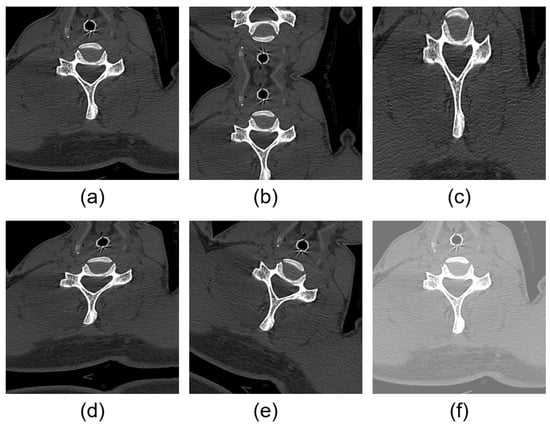

2.1. About Dataset and Its Preprocessing

2.2. Data Augmentation